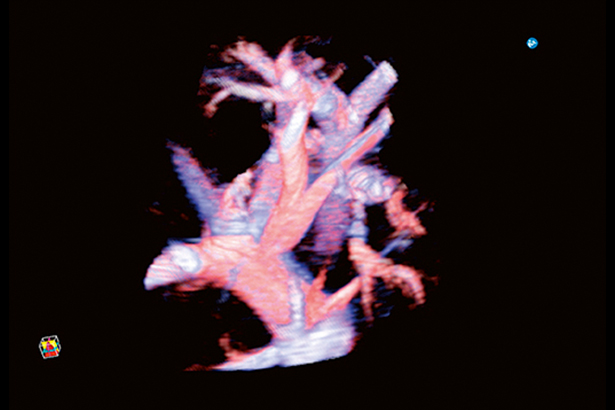

當使用寬帶iDMS探頭時,你可以調整圖像采集的聲束厚度。在對微細血流成像時,可以完整采集沿聲束方向立體擴散的血管結構。